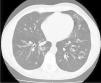

We present the case of a 42-year-old man non-smoking diagnosed with ulcerative colitis (UC) in 2004, primarily with rectal involvement, under IBD Unit follow-up. He experienced multiple outbreaks of the disease, requiring repeated corticosteroid therapy. In 2017, symptom control was achieved with vedolizumab, but the same year, he developed for the first time respiratory symptoms and chest computed tomography (CT) showed bilateral cylindrical bronchiectasis (Fig. 1).

Bronchiectasis is the most frequent pulmonary complication, typically manifesting as cough, sputum production and breathlessness. Diagnosis is confirmed via thoracic CT.1 Current treatments include inhaled corticosteroids, with oral corticosteroids for severe cases. Immunomodulators and biological therapy are third-line treatments.3